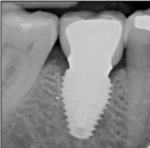

Horizontal distance from the implant platform/abutment connection to the adjacent tooth: The data indicates that as the distance between the natural tooth and the implant increases, the incidence of decay increases precipitously (Figure 2 and Figure 3). Decay occurrences range from 7.4% when the implant-tooth distance (ITD) is <2 mm to 40% when the ITD is ≥6 mm. In the 69 sites that exhibited caries, the mean ITD was 4.1 mm, and in the 338 sites without decay the mean ITD was 3.5 mm (P = .005) (Table 1). A logistic regression was performed with the single binary variable indicating whether or not the "horizontal threshold distance" was greater than 4 mm. The results show a statistically significant odds ratio of 2.00 (95% confidence interval of 1.191599, 3.350288) (Table 2.) Therefore, it is suggested that the horizontal threshold of 4 mm be considered as the "critical ITD."

Presence or absence of restorations on the adjacent teeth: A positive correlation between existence of a previous restoration and decay was found (Figure 4, Figure 5, and Table 2).